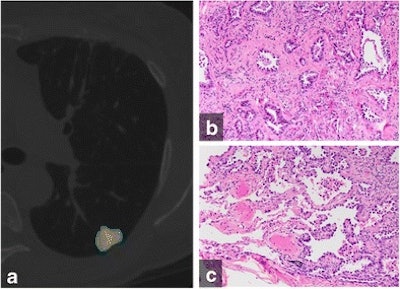

(A) Color-coded CANARY output overlay of invasive adenocarcinoma (yellow-pink-cyan). Cyan represents low-risk components, while pink and yellow indicate intermediate-risk components. The software found the nodule included 32% low-risk components, 66.9% intermediate-risk components, and 1% high-risk components. (B) Histologic image from the central area of the tumor shows the invasive acinar growth pattern (C) Histologic image from the tumor periphery showing noninvasive lepidic growth pattern and adjacent uninvolved lung parenchyma (H&E stain, 200x original magnification). Images courtesy of European Radiology.CANARY software

The CANARY software package was designed to identify pulmonary nodules that are aggressive and potentially cancerous from those that are not aggressive and potentially could be treated with less extensive surgery. It assesses voxel densities of pulmonary nodules on high-resolution CT scans and then categorizes risk based on voxel proportion and clustering. Voxel densities are classified as having low-, intermediate-, or high-risk components, each of which are color-coded as an overlay on the image.